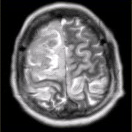

- [材料题] 女性,产后癫痫、剧烈头痛1天,意识障碍3小时。MRI显示如下图。

- 多项选择题1.关于MRI表现的描述,正确的是

A、双侧额叶、顶叶皮质肿胀,脑沟变浅

B、病变同时累及皮质及皮质下白质

C、上矢状窦流空信号消失

D、病变占位效应明显

E、病变信号均匀

F、病变邻近脑膜增厚